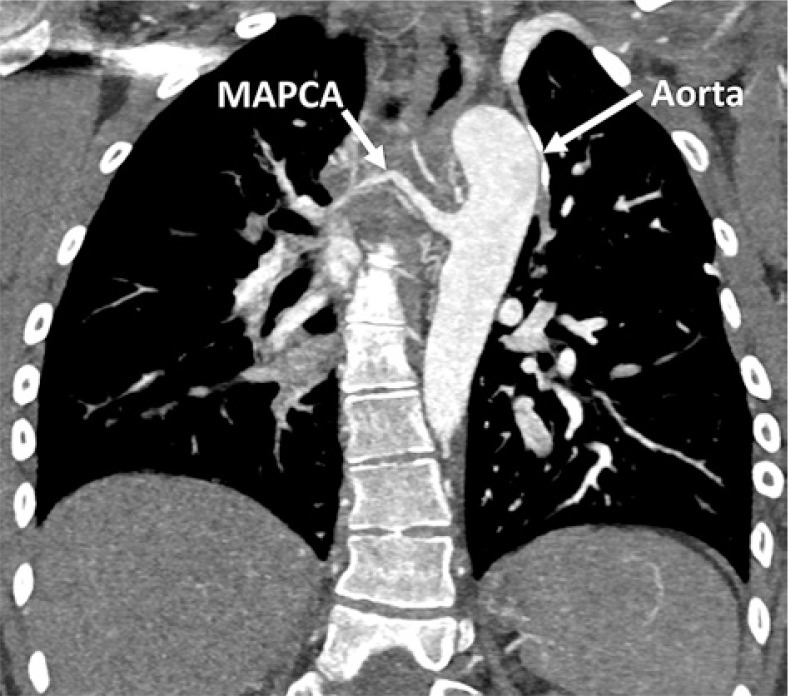

Purpose: Major aortopulmonary collateral arteries (MAPCAs) are rare congenital anomalies with significant clinical implications, often associated with congenital heart diseases like tetralogy of Fallot (TOF) and pulmonary atresia (PA). This study aimed to investigate the clinical, echocardiographic, and radiologic characteristics of MAPCAs in patients with congenital heart diseases admitted to our clinic between 2016 and 2023.

Material and methods: A retrospective analysis of 46 cases was conducted using chest computed tomography exams performed on a dual-source 128-slice CT scanner. Clinical data and radiologic characteristics were collected and analysed.

Results: The study revealed a strong correlation between congenital heart diseases and the presence of MAPCAs, with TOF, PA, and ventricular septal defect (VSD) being the most common, and it indicated that these collaterals may exist with non-diagnosed congenital heart disease. Tricuspid regurgitation and aortic insufficiency were the predominant echocardiographic findings. Radiologically, MAPCAs primarily originated from the descending aorta (type II) in 85% of cases, and their sizes ranged from ≤ 3 mm to > 10 mm, with an average of 5 mm.